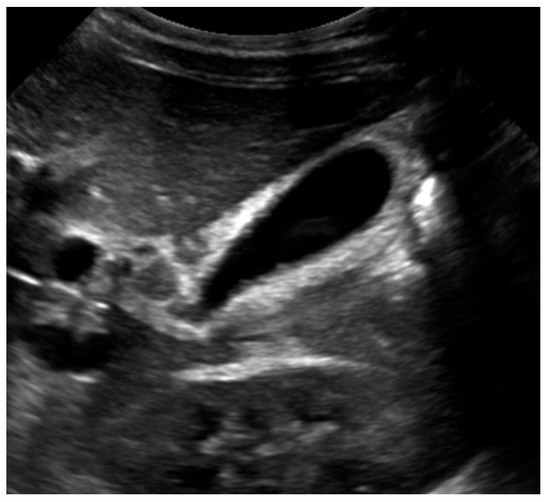

2. Case Report